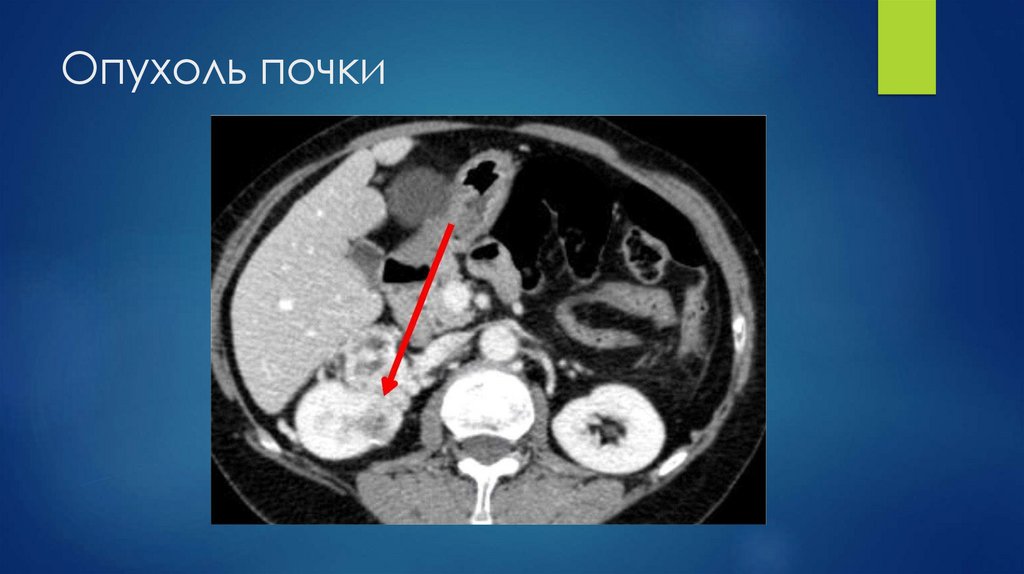

Опухоль почки

72. Опухоль почки